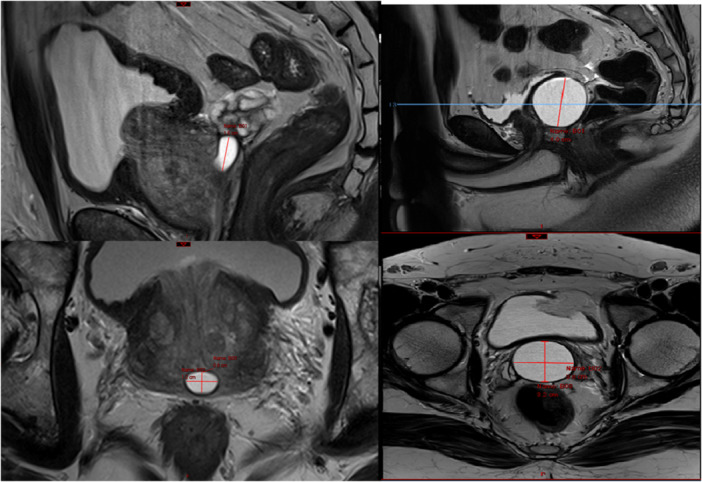

Methods: This retrospective study analyzed 5819 prostate MRI interpretations from 4990 unique patients. The primary objective was to identify congenital abnormalities, focusing on the presence of a utricle and other related anomalies. Prostates suspected to have utricles were reevaluated by genitourinary specialized radiologist and utricles size were measured.

Results: The study identified 127 patients positive for a utricle with an average age of 66 years at examination among the unique cohort. The average prostate size for patients with a utricle was 78.3 cc and the average utricle size was 0.4 cm3. Statistical analysis did not demonstrate any statistical trend between prostate size, age or PSA to utricle size. Additional congenital anomalies detected included one patient with a seminal vesicle cyst, one patient with right seminal vesicle agenesis and bilateral vas deferens agenesis, and two patients with ureterocele.